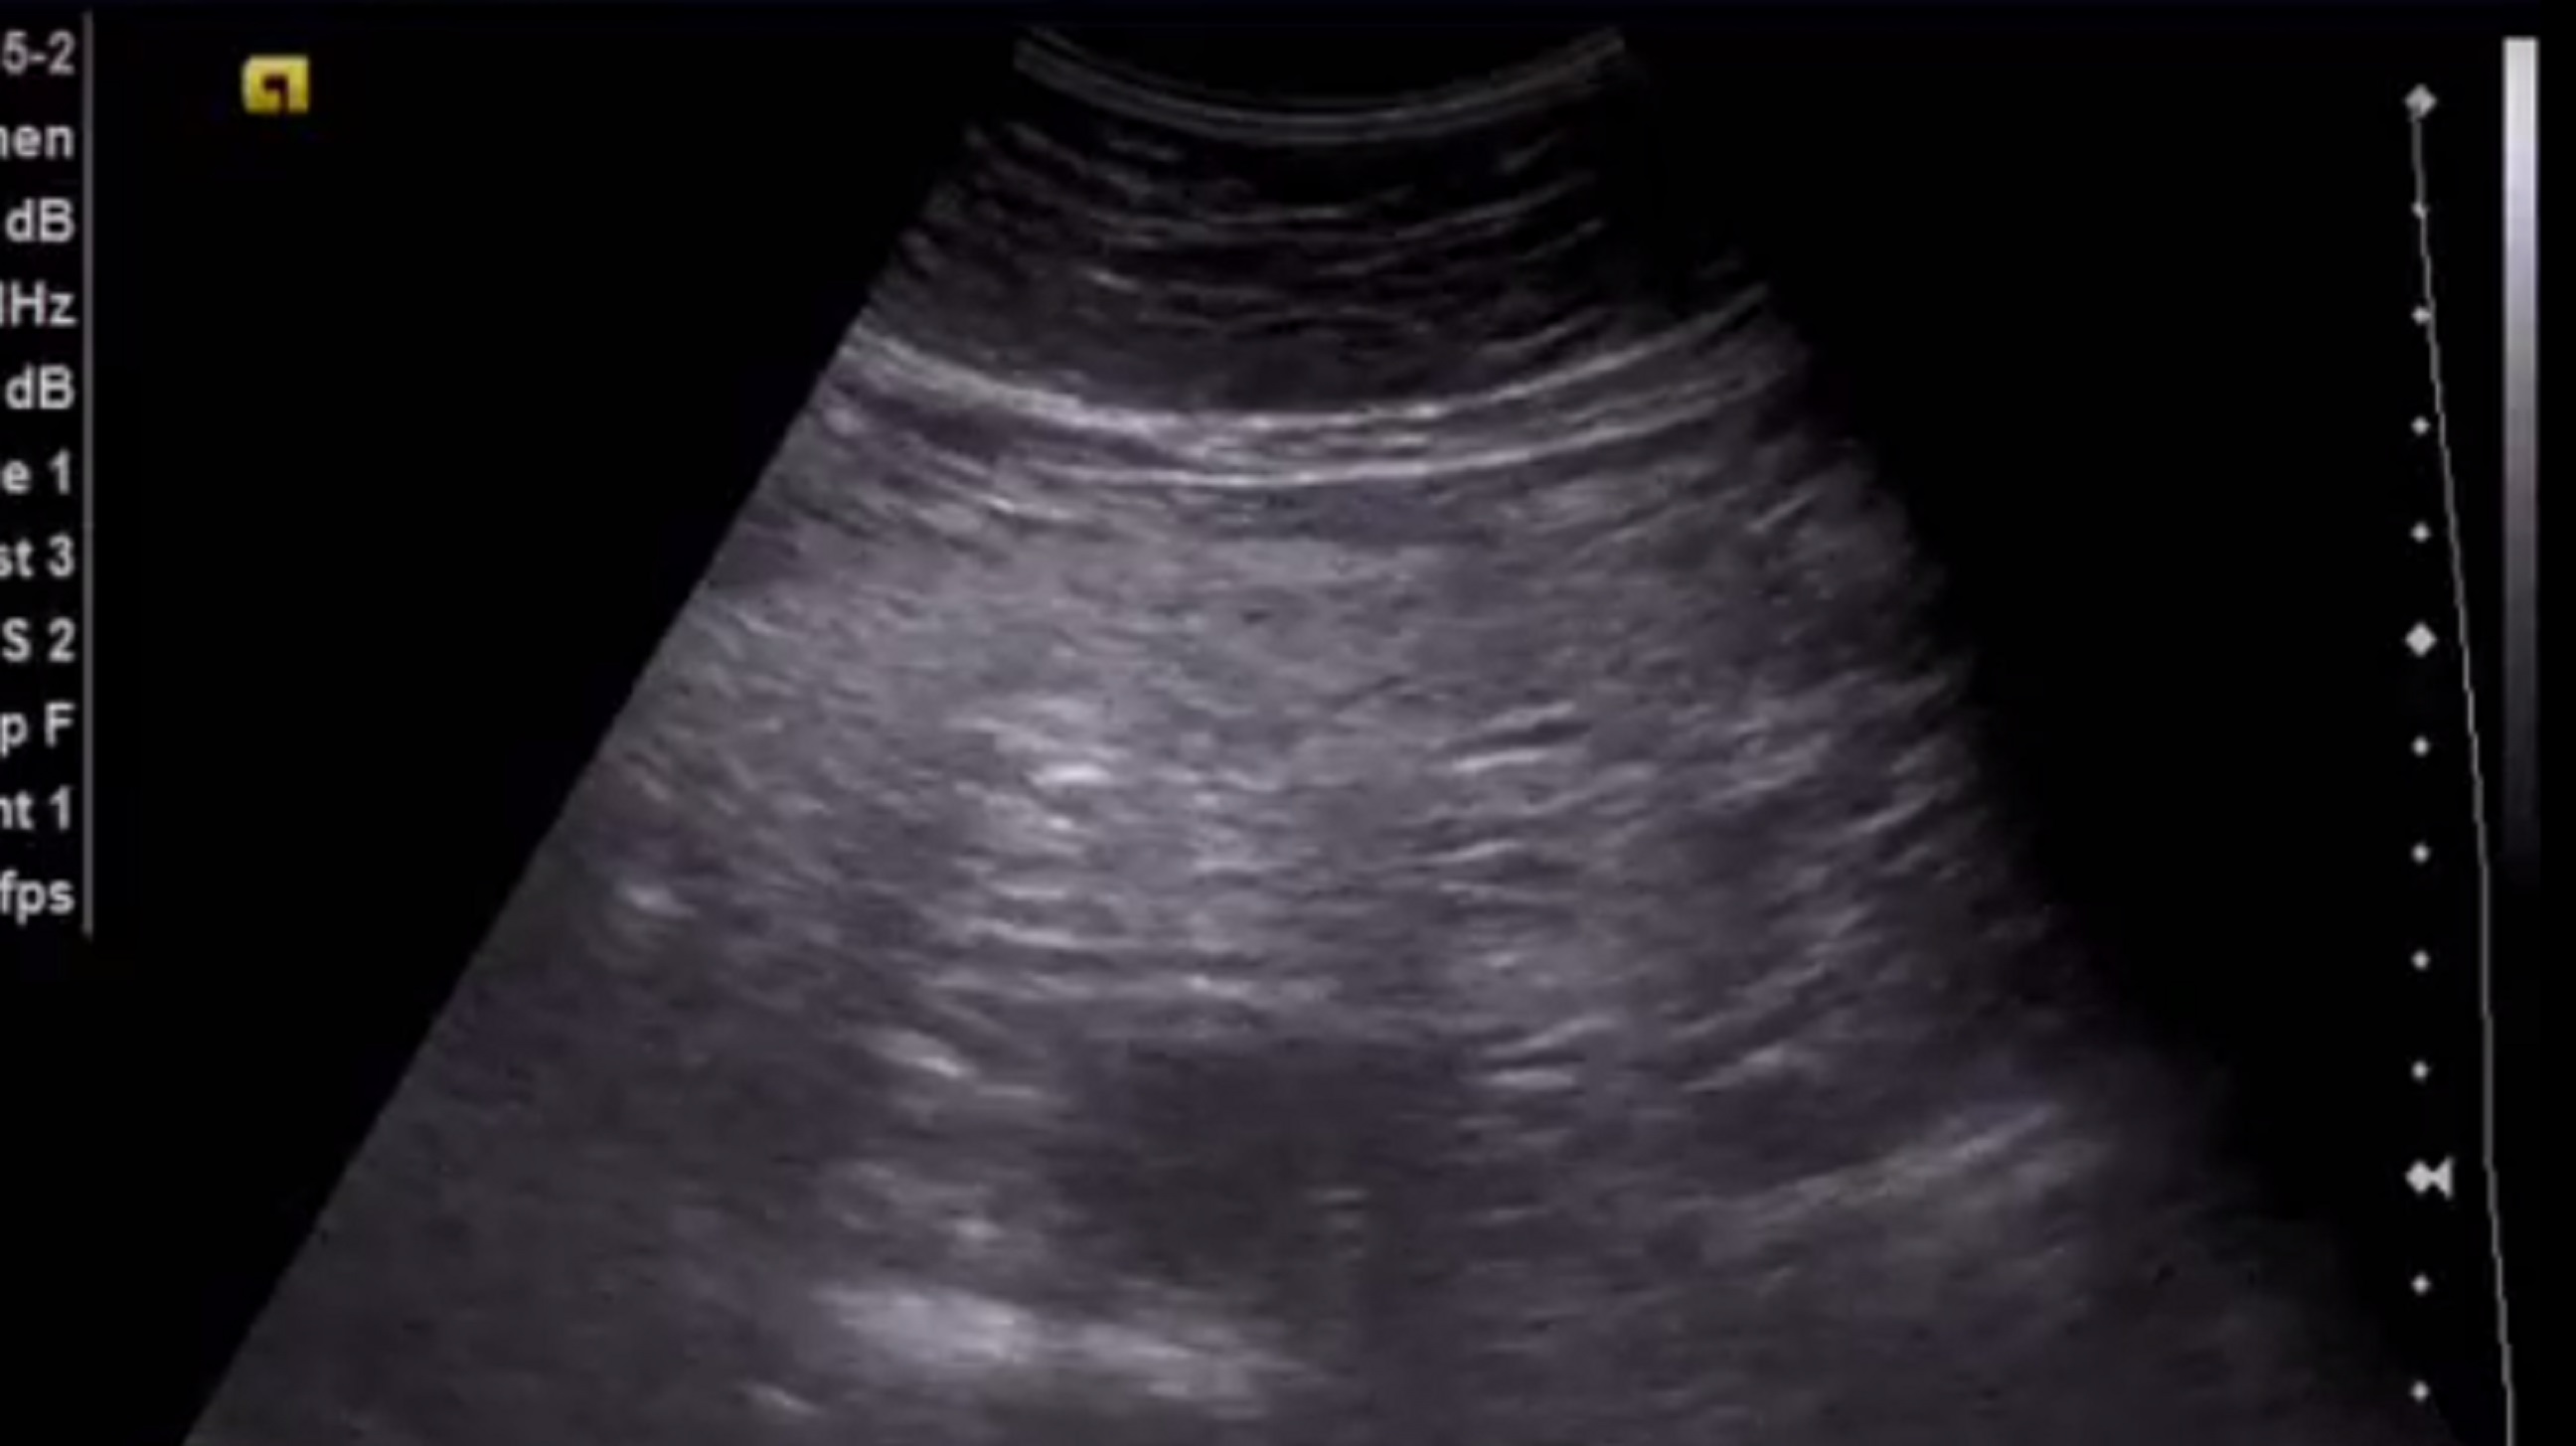

описание:

в проекции поперечно ободочной кишки, лоцируется фрагмент гиперэхогенного сальника , размером 12*4 см, с признаками кровотока на ЭДК

Заключение Уз признаки воспалительных изменений фрагмента большого сальника(инфаркт?)

посмотрите эхограммы, пожалуйста. В ролике можно сравнить эхогенность сальника в указанной области и правее